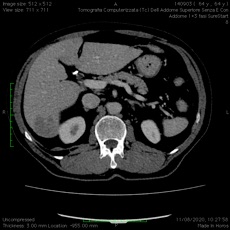

COLECISTECTOMIA DIFFICILE

Pz con pregressa colecistite acuta.

Nuovo episodio con ittero da coledocolitiasi. Bonifica della VBP mediante ERCP. Ulteriori coliche: si decide per intervento